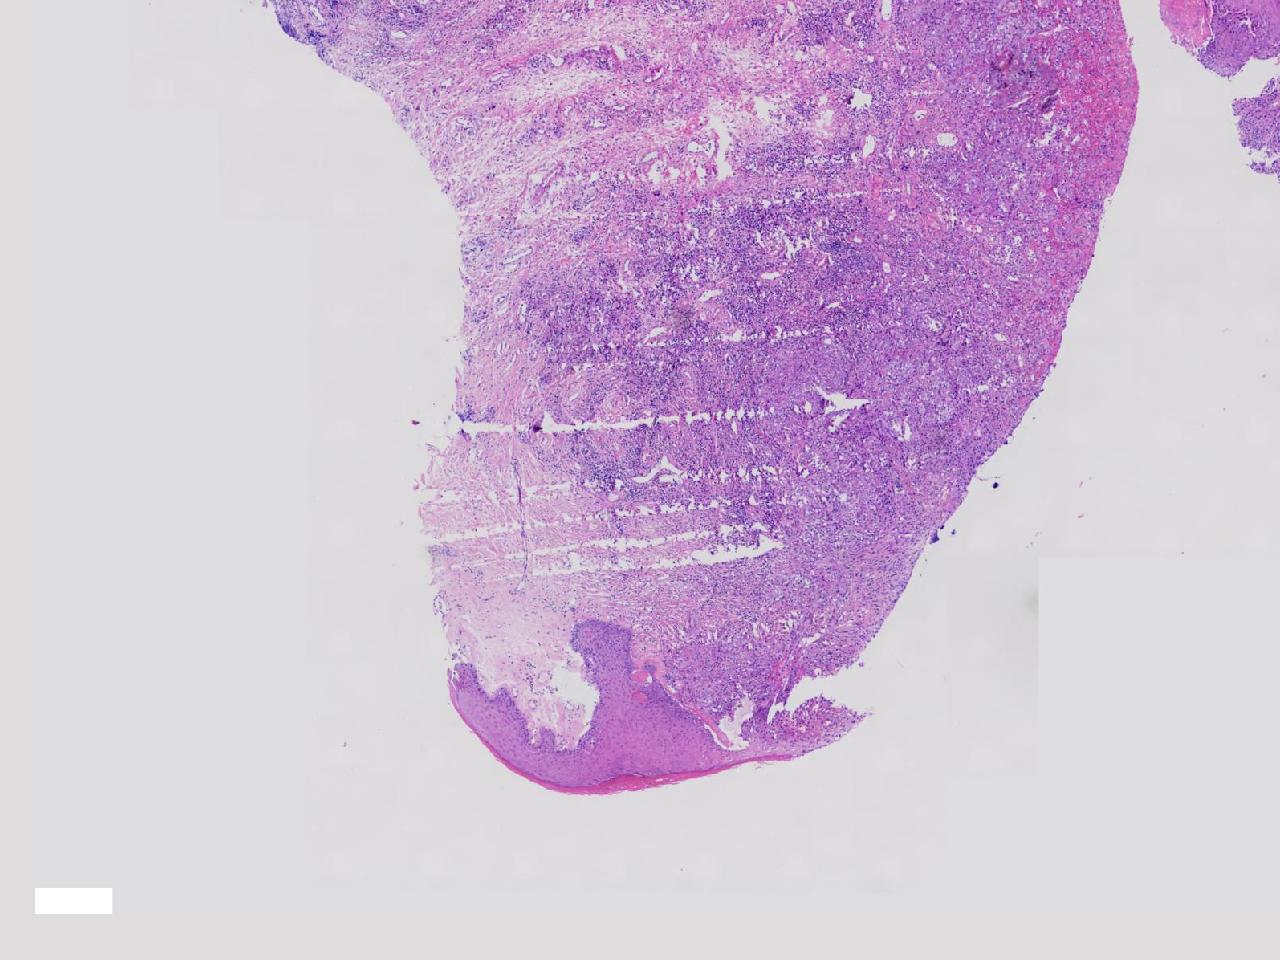

鳞癌?

性别

女

年龄

69岁

临床诊断

外阴肿物性质待查

一般病史

发现外阴肿物1月余,伴外阴疼痛,肿胀色素减退,表面分叶状。

标本名称

外阴肿物

大体所见

灰白色不整形软组织3块。

图1